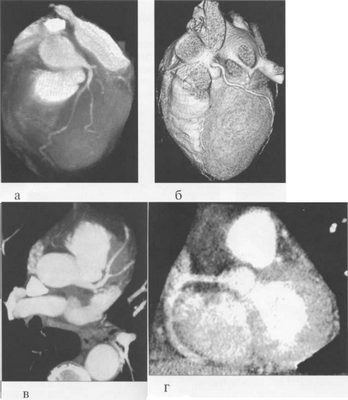

МСКТ в условиях внутривенного болюсного контрастирования позволяет визуализировать коронарные артерии (МСКТ-коронарография). Анализ состояния коронарных артерий выполняется сначала на аксиальных срезах (рис. 9.35). В постпроцессинговой обработке изображений используются различные виды реконструкций: многоплоскостные реформации (MPR), проекция максимальной интенсивности (MIP), трехмерные (VRT) (рис. 9.36).

Рис. 9.36. МСКТ-коронарограммы.

а, б — VRT-реконструкции; в — проекция максимальной интенсивности; г — многоплоскостная реформация.